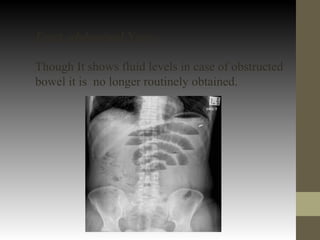

Erect abdominal Xray-

Though It shows fluid levels in case of obstructed

bowel it is no longer routinely obtained.